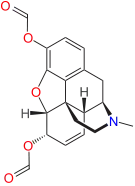

3,6-diesters of morphine

- Acetylpropionylmorphine

- 3,6-Dibutanoylmorphine

- Diacetyldihydromorphine (dihydroheroin, acetylmorphinol)

- Dibutyrylmorphine

- Dibenzoylmorphine (first designer drug)

- Diformylmorphine

- Dipropanoylmorphine

- Heroin (diacetylmorphine)

- Nicomorphine

Structures

| 3,6-diesters of morphine | ||||

|---|---|---|---|---|

Acetylpropionylmorphine Acetylpropionylmorphine |

3,6-Dibutanoylmorphine |  Diacetyldihydromorphine Diacetyldihydromorphine(dihydroheroin, acetylmorphinol) | ||

Dibutyrylmorphine Dibutyrylmorphine |

Dibenzoylmorphine Dibenzoylmorphine |

Diformylmorphine Diformylmorphine | ||

Dipropanoylmorphine Dipropanoylmorphine |

Heroin Heroin(diacetylmorphine) |

Nicomorphine Nicomorphine | ||